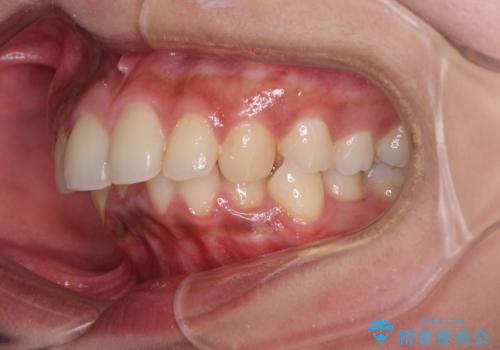

深い咬み合わせと前歯のデコボコ インビザラインによる矯正治療

- 前歯のデコボコと、食いしばりやすい咬み合わせを気にして来院された患者様です。

骨格的に下顎骨が左側に偏位しており、インビザラインでの矯正治療では奥歯の咬みにくさが残る仕上がりが懸念されましたが、新幹線での通院となるため、来院回数の少ないインビザラインでの治療を希望されました。

リスクをご説明した上で、インビザラインにより気になっている叢生と深い咬み合わせを改善していくこととしました。

治療途中では、左右ともに奥歯が咬みにくい状態が続き、問題なく噛めるようになるまでに長期間を要しました。

一方で、デコボコや下顎の前歯が隠れてしまうほどの深い咬み合わせはしっかりと改善されました。